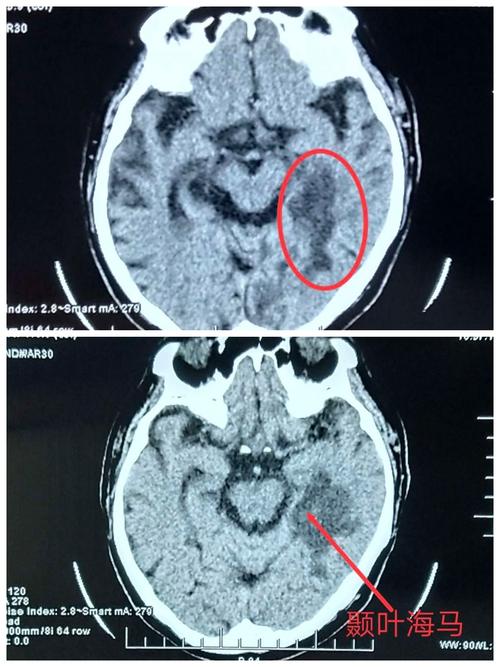

人脑海马位置ct图片,海马体MRI图像

【影像复习】海马硬化的影像诊断

头ct见左侧颞叶海马亚急性梗死灶.

轴位flair(a,b)和冠状位t2加权像(c,d)显示全脑萎缩伴双侧海马萎缩